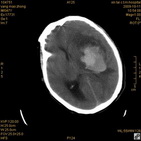

病人杨XX,男,青云街道办事处路踏泉村,住院号51666,CT号:104770。病人因“高血压脑出血”在新泰市人民医院住院治疗5天,治疗效果不佳转入我院,复查CT示左基底节血肿,病人昏迷状态,给予血肿清除术,术后2天复查CT,血肿完全清除,病人恢复好,治疗效果满意。附病人术前术后CT片资料如下。

术前CT

术前CT1 术前CT2 术前CT3 术前CT4